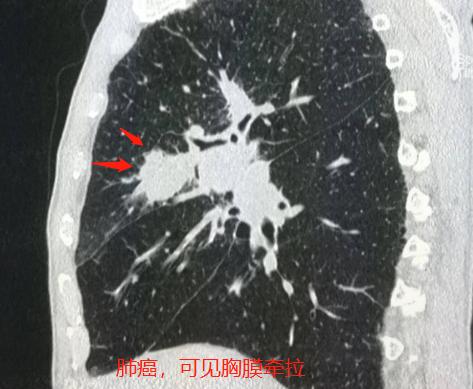

发现脑内多发类圆形低密度影,内部似乎还有稍高密度小结节,可疑脑转移瘤,于是进一步肺CT检查:

果然发现了右侧肺癌脑转移,伴有胸膜牵拉和增厚。